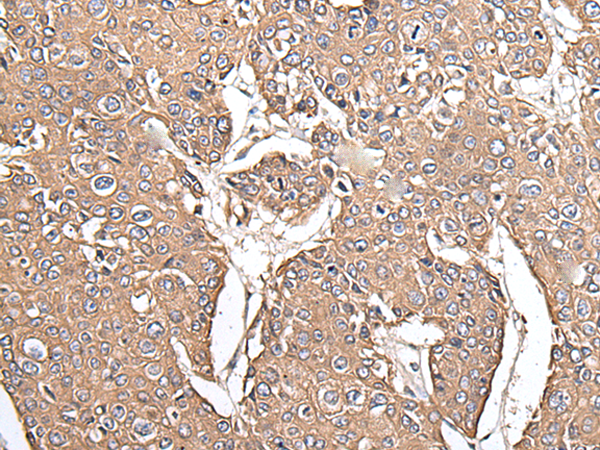

IHC positive control: |

Human prostate cancer and human lung cancer |